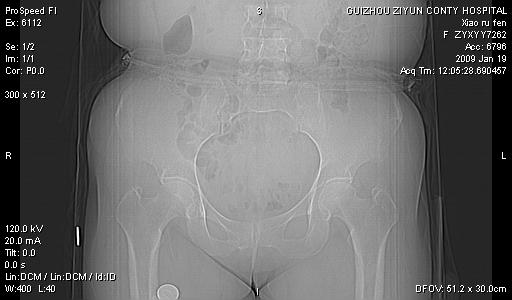

以下是引用zbp537在2009-1-19 14:25:00的发言:[br]考虑两个诊断:1、皮脂腺囊肿伴感染。2、脓肿。[br]诊断依据:[br]1、肿块为低密度,边界较清,和皮肤相连,周围结构清晰,未见受累及。[br]2、诊断脓肿是因为其内密度不均匀,当然要结合病史,因为脓肿临床上肯定表现为红肿热痛,也希望楼主把病史提供全面些,这些便于讨论。

以下是引用zbp537在2009-1-19 14:25:00的发言:[br]考虑两个诊断:1、皮脂腺囊肿。2、脓肿。[br]诊断依据:[br]1、肿块为低密度,边界较清,和皮肤相连,周围结构清晰,未见受累及。[br]2、诊断脓肿是因为其内密度不均匀,当然要结合病史,因为脓肿临床上肯定表现为红肿热痛,也希望楼主把病史提供全面些,这些便于讨论。